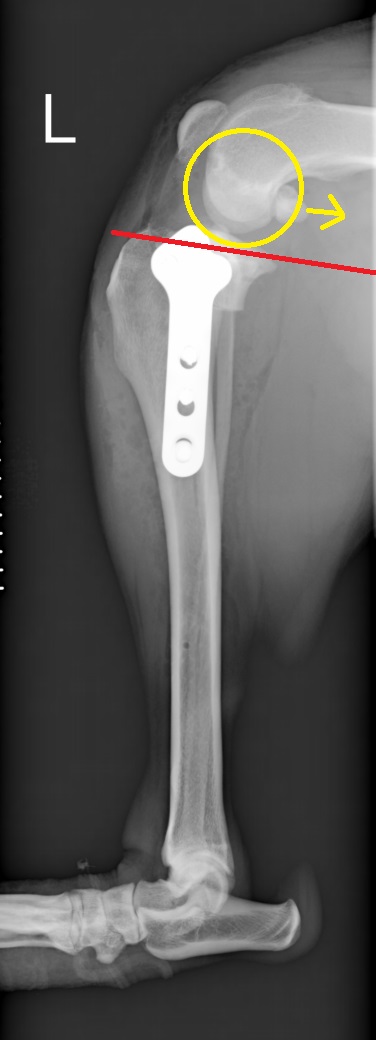

赤直線が脛骨高平部角、青・黄色矢印は大腿骨が滑り落ちてしまう力のベクトル

脛骨高平部水平化骨切術(Tibial Plateau Leveling Osteotomy 以下TPLO)は脛骨近位に半円曲線の骨切りを加え、

近位骨片を回転させて金属インプラントで固定し、脛骨高平部角を減少させることで、大腿骨が後ろに滑り落ちる力を無くし、前十字靭帯機能が消失した膝関節の動的安定化を図ります。

術後、脛骨高平部角がほぼなくなったことが分かります